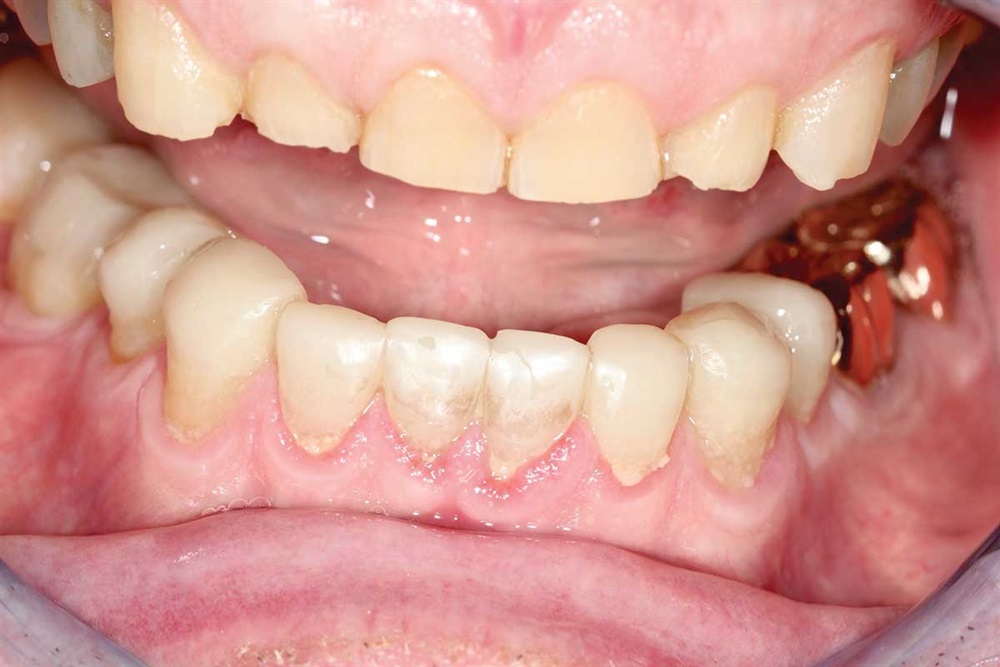

Fig. 3: Lower incisors. The patient’s dentists in Ontario wanted to do ortho for 18–24 months and then restorative crowns with many elective root canals, to the tune of a nice luxury car.

Show Your Work

Fig. 14–16: It is hard to see, but the patient’s bicuspids nearly miss in occlusion because the upper bicuspids are buccal to his lower bicuspid. One reason for ortho would have been to expand the lower arch to get more occlusion on the bicuspids.